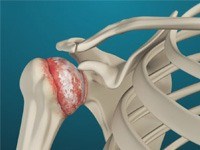

Shoulder Arthritis

The term arthritis literally means inflammation of a joint, but is generally used to describe any condition in which there is damage to the cartilage. Damage of the cartilage in the shoulder joint causes shoulder arthritis.

Rotator Cuff Tear

Rotator cuff is the group of tendons in the shoulder joint providing support and enabling wider range of motion. Major injury to these tendons may result in tear of these tendons and the condition is called as rotator cuff tear. It is one of the most common causes of shoulder pain in middle aged adults and older individuals.

Rotator cuff is the group of tendons in the shoulder joint providing support and enabling wider range of motion. Major injury to these tendons may result in tear of these tendons and the condition is called as rotator cuff tear. It is one of the most common causes of shoulder pain in middle aged adults and older individuals. It may occur with repeated use of arm for overhead activities, while playing sports or during motor accidents.

Reverse Total Shoulder Replacement

Reverse total shoulder replacement, is an advanced surgical technique specifically designed for rotator cuff tear arthropathy, a condition where the patient suffers from both shoulder arthritis and a rotator cuff tear.